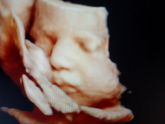

5 июня 2020 14:10 Вот в сравнении. Так лучше понять. Разница 1 неделя. 30 недель и 31 неделя. Всё таки кажется опустился.